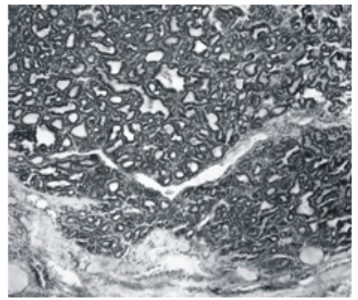

Опухоль характеризуется медленным ростом. Часто заболевание своевременно не диагнос-тируется, и имеющееся новообразование расценивается как аденома щитовидной железы. На разрезе новообразование имеет вид округлого узла коллоидного вида, с четко очерченной границей. На фоне каменистой плотности могут быть мягкие участки, которые связаны с некрозом опухоли в данном месте железы.

Рис. 1. Нативный препарат. Кистозная трансформация кровоизлияния в опухолевой ткани фолликулярного рака щитовидной железы

Рис. 2. Нативный препарат. Новообразование в виде округлого узла коллоидного вида